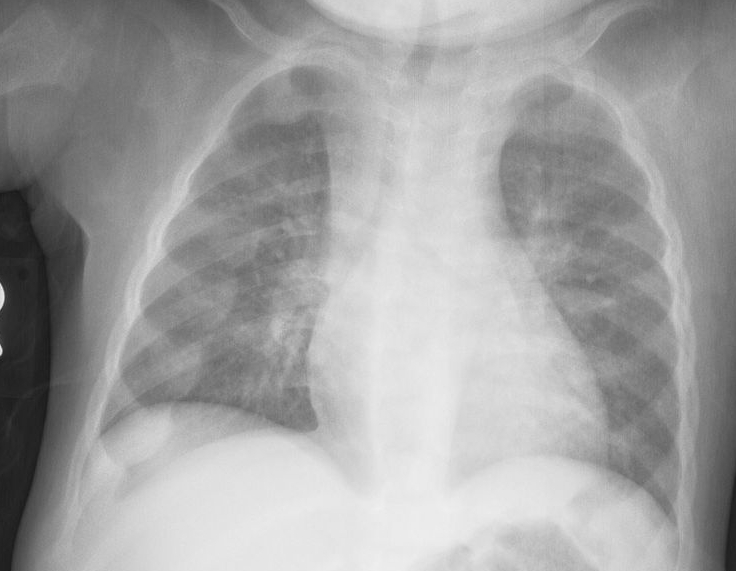

Jeune Syndrome

Aka asphyxiating thoracic dystrophy

symptoms: short stature, long and narrow thorax, hypoplastic lungs, fibrotic liver, and short limbs. Death is common, a result of pneumonia or asphyxia because of the abnormally shaped thorax.,